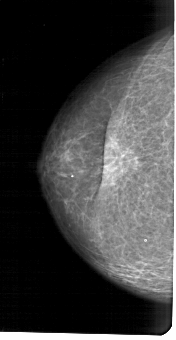

A_1655_1.RIGHT_MLO

RIGHT_MLO LINES 5491 PIXELS_PER_LINE 3286 BITS_PER_PIXEL 12 RESOLUTION 43.5 NON_OVERLAY